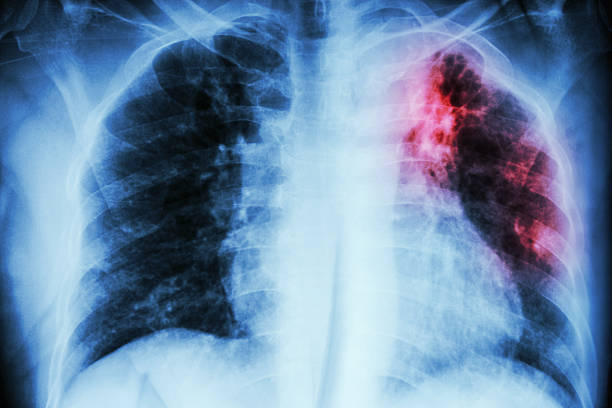

폐섬유화증은 폐조직 내 결손 및 염증에 의해 섬유화 과정이 일어나서, 건강한 폐조직이 염증과 섬유화에 대한 대체물질로 치환되는 질환입니다. 이로 인해, 섬유화된 조직은 신축성이 없고, 호흡기능이 저하됩니다. 따라서 다른 질병과 마찬가지로 초기에 적절한 치료를 받는 것이 중요하기 때문에 이번 시간에는 폐섬유화로 인한 증상들에 대해 정리해보겠습니다.

호흡 곤란은 폐섬유화증의 가장 대표적인 증상 중 하나입니다. 일반적으로 증상이 더해지는 것으로 나타나며, 물리적인 활동이나 감정적인 스트레스로 발생할 수도 있습니다. 호흡 곤란은 폐조직의 결손으로 인해 공기의 흐름이 제한되어 발생합니다. 호흡 곤란이 있을 경우 심한 경우에는 폐활량 감소로 인해 산소공급이 충분하지 않아 발생할 수 있는 산소부족증상에 의해 혼수상태에 이르기도 합니다.

만성 기침은 호흡 곤란과 함께 폐섬유화증의 대표적인 증상 중 하나입니다. 기침은 호흡기의 염증 및 결손으로 인해 발생합니다. 이 증상은 급성기침과 달리 더욱 지속적이며, 가끔은 거의 쉬지 않는 경우도 있습니다.